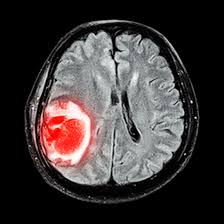

Some genes control when our cells grow, divide into new. The standard treatments for brain tumors include surgery, radiation and chemotherapy. (cnn)the incidence rate of aggressive malignant brain tumors in england has more than doubled in recent decades, and a new study questions what could be driving that rise. Unlike cancers that start in other parts of the body, tumors that start in the brain or spinal cord rarely spread to distant organs. Metastatic tumors to the brain affect nearly one in four patients with cancer, or an estimated 150,000 people a year. The cancer cells break away from the primary tumor and travel to the brain, usually through the bloodstream, then commonly go to the part of the brain called the cerebral hemispheres or to the cerebellum. What you need to know. Soft tissue cancers, like those that develop. Some of the cancers that are on the rise are preventable. We found that the incidence rate of all pediatric brain tumors has been on a gradual but steady increase from 1973 to 2008 (p < 0.001). A new study has revealed that 10 years of cellphone use resulted in an average 290% increased risk of brain tumor development. Cancer is on the rise among young people over the past decade, cancers associated with obesity show some of the most troubling increases affecting young adults and adolescents. Dna is the chemical that makes up our genes, which control how our cells function.

Brain and spinal cord tumors, like other tumors, are caused by changes in the dna inside cells. Treating brain tumors takes a team of. Metastatic tumors to the brain affect nearly one in four patients with cancer, or an estimated 150,000 people a year. Nearly 78,000 new cases of primary brain tumors are expected to be diagnosed this year. Unlike cancers that start in other parts of the body, tumors that start in the brain or spinal cord rarely spread to distant organs. It is also called a central nervous system tumor. (cnn)the incidence rate of aggressive malignant brain tumors in england has more than doubled in recent decades, and a new study questions what could be driving that rise. This information is about primary brain tumors. In general, brain tumors are more common among older people, but statistics even show an increase in brain tumors in kids. Metastatic brain tumors (also called secondary brain tumors) are caused by cancer cells spreading (metastasizing) to the brain from a different part of the body.; Addressing risk factors like smoking, obesity, sedentary lifestyle, and exposure to harmful environmental surroundings can go a long way toward improving your health and reducing your cancer risk. Soft tissue cancers, like those that develop. The standard treatments for brain tumors include surgery, radiation and chemotherapy.